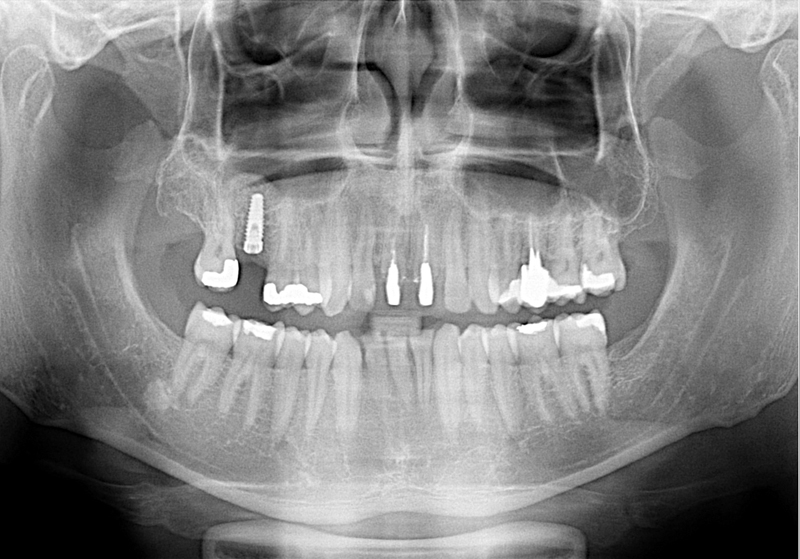

Při ztrátě molárů a premolárů v horní čelisti a jejich náhradě implantáty se často setkáváme s nedostatečnou

vertikální nabídkou kosti pod čelistní dutinou, často doprovázenou i nedostatečnou horizontální nabídkou a sníženou kvalitou kosti (v oblasti 2. premoláru v 50%, v oblasti moláru až v 80% případů nedostatečná kostní nabídka)